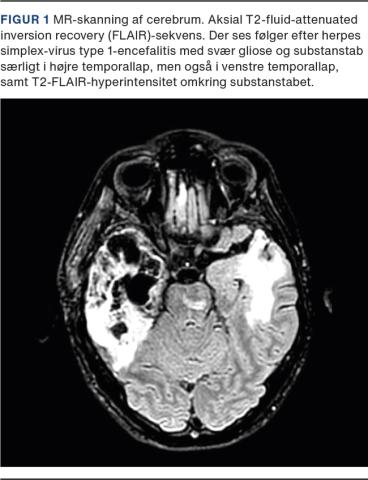

En 27-årig mand blev indlagt med postherpetisk anti-NMDAR-AE. Ved vurdering var han delirøs, psykotisk og til fare for sig selv og andre. Det var nødvendigt at bæltefiksere ham, og han blev dobbeltindlagt i psykiatrisk og neurologisk regi.På indlæggelsestidspunktet var han under rehabilitering for HSV1-encefalitis, som var debuteret 11 uger forinden med hovedpine, feber og konfusion. Diagnosen blev bekræftet ved fund af et leukocytniveau (totalt/mononukleære) på 278/275 × 106/l og HSV1-DNA i cerebrospinalvæsken, og han blev behandlet med intravenøst givet aciclovir. Tilstanden blev kompliceret af livstruende hjerneødem, og der blev foretaget dekompressiv højresidig hemikraniektomi. Efter fem ugers indlæggelse var han stabil og blev overflyttet til genoptræning. Her var han fortsat kognitivt påvirket med svær amnesi og apraksi, men søvnen var stabil, og han gik uden støtte samt spiste og drak selvstændigt. Tre til fire uger inde i rehabiliteringsforløbet udviste han tiltagende katatone symptomer i form af spisestop, partiel mutisme, stereotype bevægelser, mekanisk monoton tale, negativisme, agitation og udadreagerende adfærd. Han var også tiltagende psykotisk samt havde vrangforestillinger og synshallucinationer. Der blev foretaget MR-skanning af hjernen (Figur 1), og lumbalpunktur blev gentaget, hvorved man fandt et let forhøjet leukocytniveau (totalt/mononukleære) på 13/13 × 106/l), forhøjet proteinniveau (1,14 g/l), negativ HSV1-DNA, men positiv NMDAR-IgG-antistof.